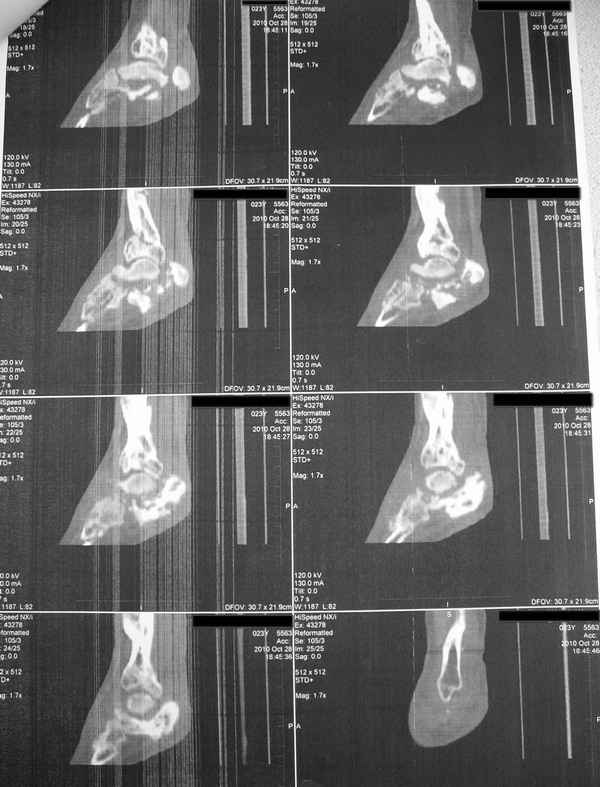

Молодая девушка со сросшимися многооскольчатыми переломами пяток и голеней.

Young girl with fractures of the calcaneus

Больная Н., 25 лет, падение с высоты (2008 г.). Жалобы на боли в области голеностопных суставах, в области пяток при ходьбе. Лечилась в аппаратах внешней фиксации по поводу открытых оскольчатых переломов обеих голеней, переломов пяток. Далее по поводу несросшихся переломов голеней –ЧКОС аппаратами внешней фиксации. Переломы срослись, аппараты демонтированы весной 2010г. В левой пяточной области в месте проведения спицы имеется сукровичное отделяемое. При ревизии гноя нет. Чем помочь девушке?

Patient N., age 25, falls from heights (2008). Complaints of pain in the ankles, in the heel when walking. She was treated by external fixation on open comminuted fractures of both legs, fractures of the calcaneus. Then she was treated by external fixation from nonunion of both legs. Now fractures are fused, apparatuses removed in the spring of 2010. How to help a girl?